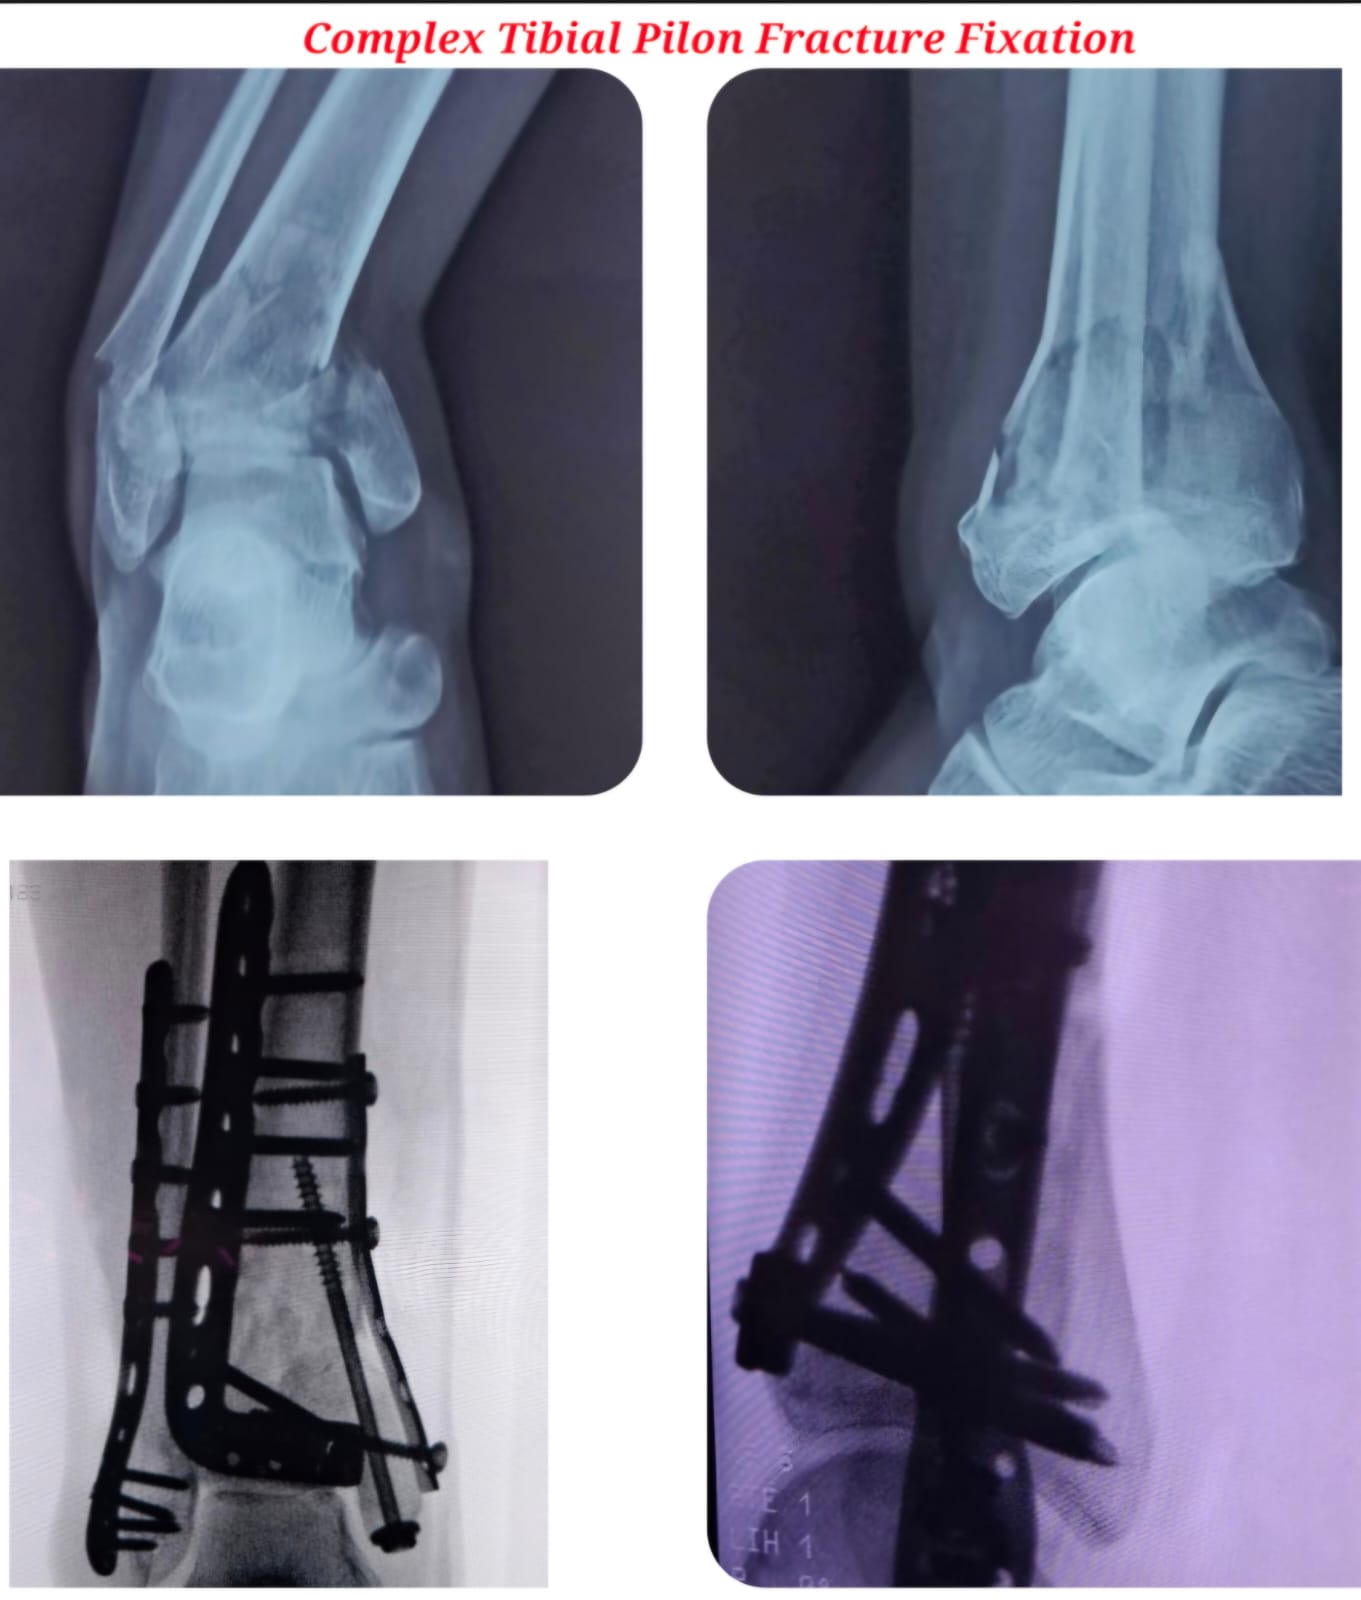

Diagnosis begins with detailed clinical evaluation supported by advanced imaging such as X-rays, CT scans, and MRI. Treatment options are customized based on the type and severity of injury and may include casting, splinting, closed reduction, or surgical intervention to restore proper alignment and stability.

My first operation ever (hopefully the last). The experience in the Operation Theatre was mind blowing. DK sir, all docs, and supporting staff were extremely cool right from the time I got into the Operation Theatre. I had to get my Ankle operated (2 fractures). I felt I was in safe hands throughout.